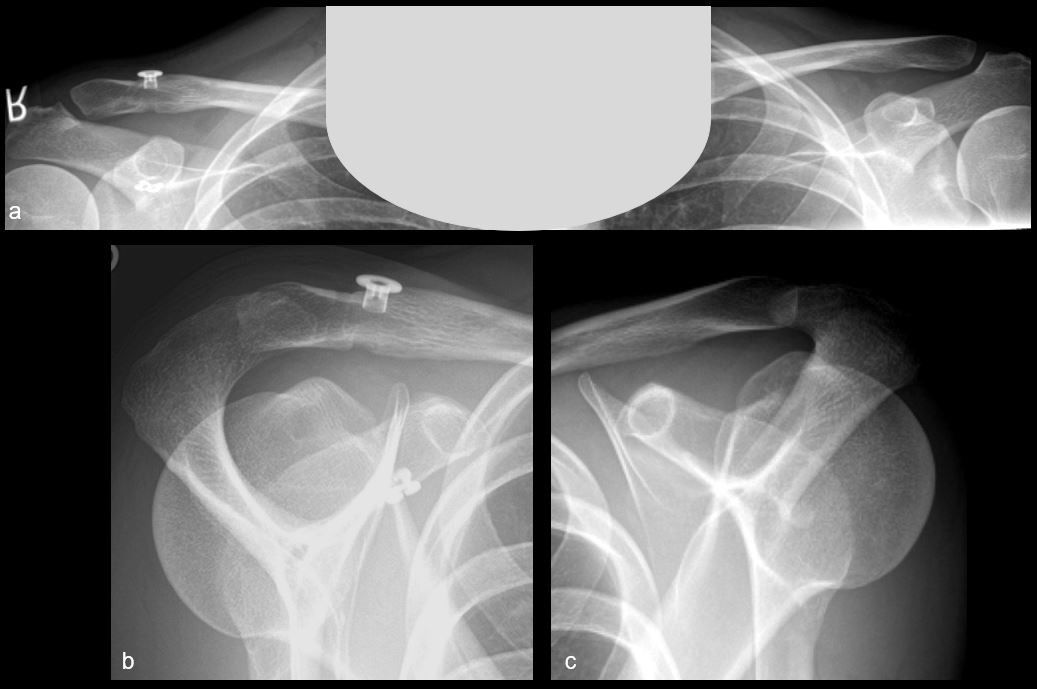

Reduction of the AC-joint and coracoclavicular stabilization

The inferior sutures of the low-profile Tightrope device (Arthrex, Naples, Florida) are attached to the proximal eyelet of the first nitinol wire and pulled from the other end through the clavicle and coracoid (Fig. 6a). Under arthroscopic control, the sutures are retrieved via the anteroinferior portal (Fig 6b & c). A DogBone button (Arthrex, Naples, Florida) is attached to the inferior sutures (Fig 6d). By using a clamp and by pulling from superior, the inferior button is placed under the coracoid arch. Under arthroscopic control, the button is placed in the correct position (Fig. 6e). By pulling the sutures of the low-profile device alternating the double button system tightens itself. The two suture pairs are pulled alternating until the superior button is on the level of the clavicle enabling an anatomical reduction of the AC-joint (Fig. 6f & g). A suture tensioner is mandatory for a proper tensioning of the Tightrope device. 80-100 N are applied for each suture which can lead to some overreduction of the AC-joint that is accepted (Fig. 6h). The anatomical reduction of the AC-joint should be controlled using the image-intensifier. Once reduction is achieved, the sutures are knotted securely. Before cutting the sutures on a low profile, to reduce knot stack, we recommend knotting the sutures of the device to provide sufficient stability and avoid early redislocations.

Arthroscopic techniques for AC-joint reconstruction became more popular in recent years due to multiple benefits i.e. a minimally invasive approach, hence a satisfying cosmetic outcome and a possible reduction of the risk of infection, the possibility to treat concomitant glenohumeral lesions and one-step procedure character using implants without the necessity of later implant removal. The combined arthroscopically-assisted and image intensifier-controlled Double-Button technique with an additional AC cerclage represents a safe procedure which enables an anatomical reduction of the AC joint. The combined coracoclavicular and acromioclavicular reconstruction allows a stabilization in the vertical and horizontal plane. The low-profile device facilitates self-tensioning allowing a simplified anatomical reduction process. The recessed TightRope hole design reduces the risk of a knot stack profile, aiming to reduce knot stack profile leading to impaired wound healing or persistent pain and hence revision surgery.